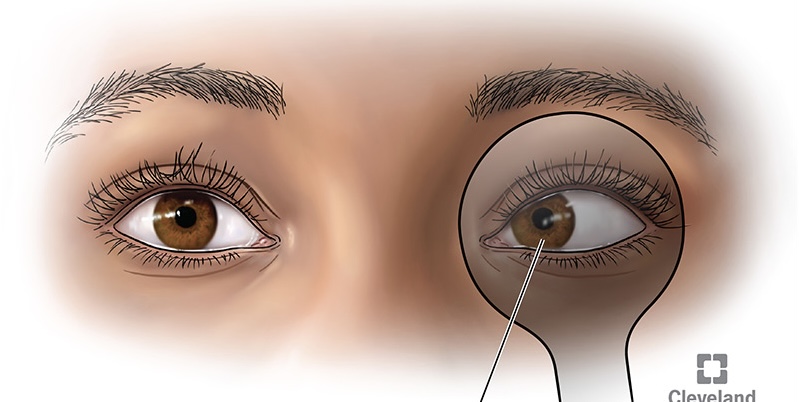

pterygium

a thickening of the bulbar conjunctiva that extends across the nasal side.